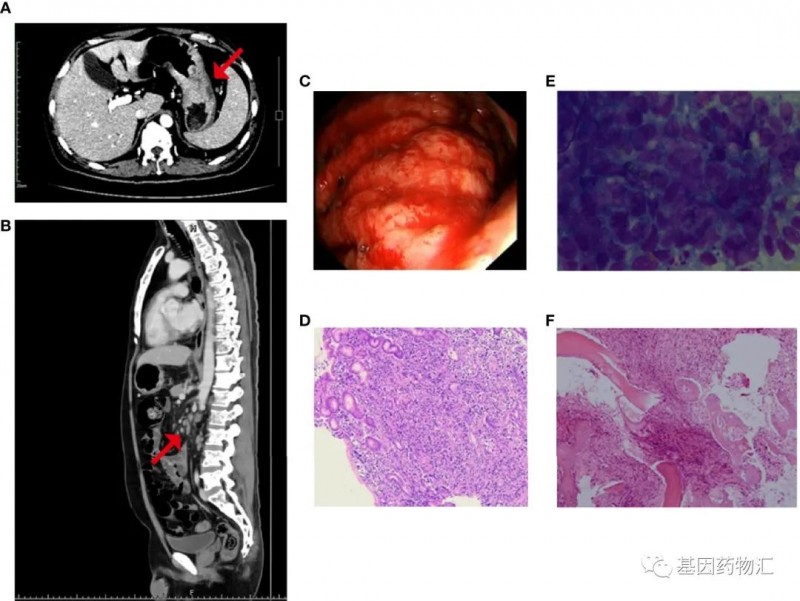

另一位47岁的胃癌患者,基本状态较差:无法行走、血小板严重降低(14×10^9/L)。CT显示患者胃底及胃体增厚,胃周、肝门、腹膜后、纵隔及双侧肺门区多处淋巴结转移,且存在广泛的全身性骨转移(右侧额骨眶上缘、双侧锁骨、双侧肩胛骨、多根肋骨、胸椎、腰椎和骶椎、骨盆骨、右侧肱骨和双侧股骨上部)。

二代测序结果提示患者存在MET扩增及MET ST7重排,微卫星稳定,肿瘤突变负荷中等(6.3个突变/Mb),分期为ⅣB期。

患者接受了对症的治疗(红细胞、血小板及促血小板生成药物输注等),并且尝试了纳武单抗治疗。但输注药物后,患者的血小板迅速下降。后患者接受了低剂量的S-1化疗,治疗3天后出现黑便和鼻粘膜出血,血小板计数继续降低。

至入院21天,患者开始出现发热、肺部感染、急性左心衰竭,病情危笃!结合患者的情况,医生最终为他选择了赛沃替尼(沃利替尼,savolitinib)方案。

令人欣喜的是,塞沃替尼方案的效果非常显著!治疗4天后,患者血小板恢复至27×10^9/L,骨痛等症状也明显开始缓解;治疗18天,患者血小板恢复至81×10^9/L,达到了出院的标准。

至治疗55天回访时,患者的血小板(188×10^9/L)、血红蛋白(111g/L)以及白细胞都恢复到了正常水平,肿瘤标志物也明显降低,CT复查胃底和体壁变薄,淋巴结缩小,骨髓图片显示无转移性癌细胞。根据标准,患者已经达到了部分缓解。